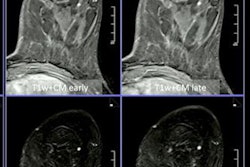

The Ota team wanted to add noncontrast sequences from MRI, such as T1- and T2-weighted imaging combined with diffusion-weighted imaging and test this approach's performance.

Noncontrast sequences from MRI, such as T1- and T2-weighted imaging, could further help diffusion-weighted breast imaging, according to research presented May 9 at ISMRM 2022.

Noncontrast sequences from MRI, such as T1- and T2-weighted imaging, could further help diffusion-weighted breast imaging, according to research presented May 9 at ISMRM 2022.The readers were comparable in their respective analyses. They had an average sensitivity of 79.15% and an average specificity of 89.45%. The researchers also found that apparent diffusion coefficient (ADC) measurements were significantly lower among malignant lesions (p < 0.001).

Ota said this approach to high-resolution DWI allowed for detailed morphological evaluation similar to contrast-enhanced MRI and enabled radiologists to evaluate lesions with "excellent" performance.